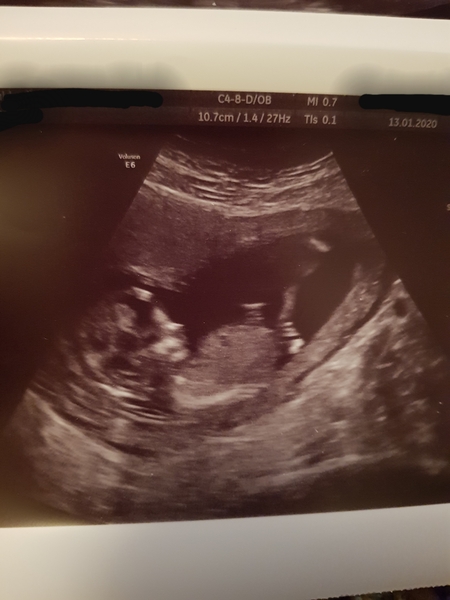

Had my 12 wk scan yesterday - DH couldn't go in the end because of his shingles anyway. EDD is now 23rd July I think I will go over though.

Baby was super active and wiggly, looks just like a really tiny person now not just a blob!

No concerns flagged just waiting on my screening results to come back.

Congratulations @hairsprayBabe we have the same EDD! What a lovely scan photo!

What a gorgeous pic! @HairsprayBabe

I was thrilled with how much you can see! Very long legged baby as well!

We are having a surprise in regards to it's sex but I think it might be a boy based on nothing at all. Thoughts and guesses welcome Grin

Wow what a wonderful scan picture @HairsprayBabe 😀

Aww @HairsprayBabe that picture is ADORABLE! Smile

I'm getting boy vibes Crown Wink